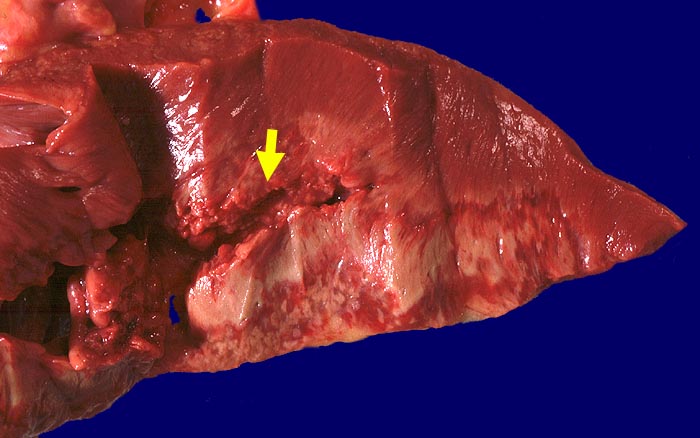

Subakuter Myokardinfarkt der Vorderwand mit Ruptur

Scharf begrenztes lehmfarbenes infarziertes Areal umgeben von einem breiten roten Randsaum Granulationsgewebe. Rupturstelle im Bereich des Granulationsgewebssaums.

Subakuter Myokardinfarkt von Vorder- und Hinterwand. Myokardruptur mit Hämatoperikard. Schwer stenosierende Sklerose von Ramus circumflexus der linken Koronararterie und der Arteria coronaria dextra.